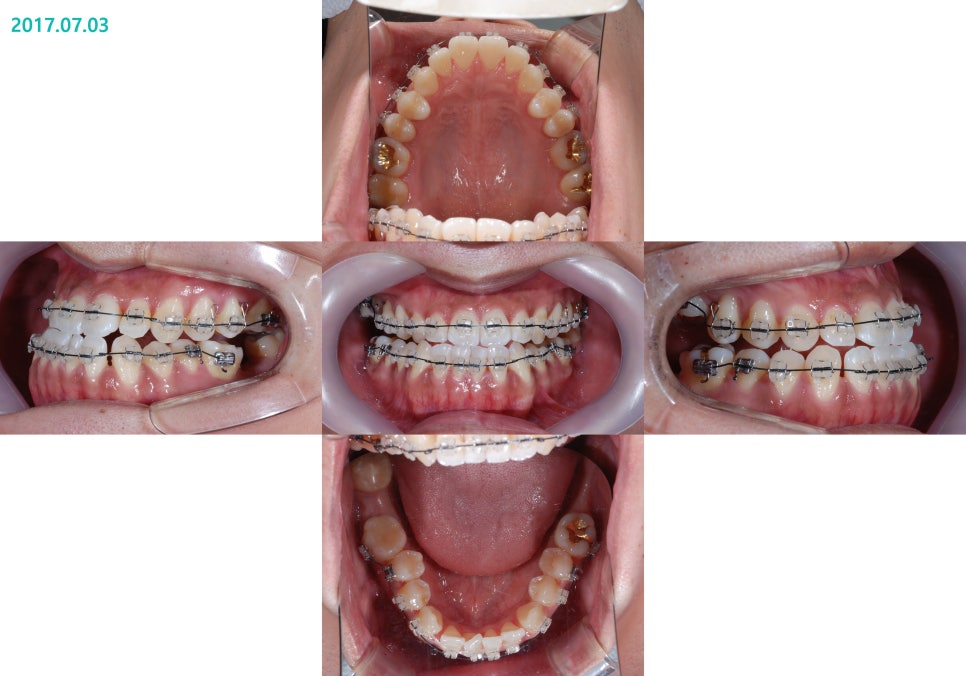

½ÉÇÑ ÁÖ°ÆÅÎ ¹×

½ÉÇÑ ¾È¸éºñ´ëĪÀ¸·Î ³»¿øÇÏ¿´°í

ºñ¼ö¼ú ÁÖ°ÆÅÎ ±³Á¤Ä¡·á¸¦ ÁøÇàÇϰí ÀÖ½À´Ï´Ù.

½ÉÇÑ ÁÖ°ÆÅÎ, ½ÉÇÑ ¾È¸éºñ´ëĪÀÇ

ºñ¼ö¼ú ÁÖ°ÆÅÎ ±³Á¤Ä¡·á Àü

ºñ¼ö¼ú ÁÖ°ÆÅÎ ±³Á¤Ä¡·á ÈÄÀÔ´Ï´Ù.